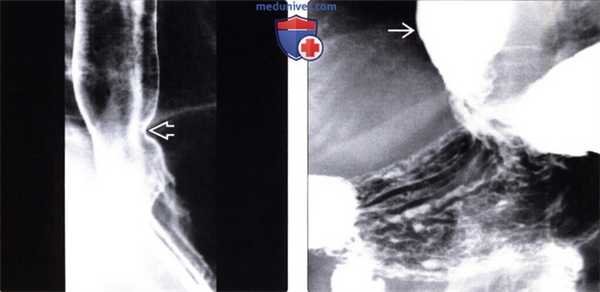

(Слева) На рентгенограмме пищевода, выполненной во время рентгеноскопии у мужчины 50 лет определяется отсутствие первичной перистальтики и глубокие, периодические третичные сокращения стенки пищевода. Просвет пищевода слегка расширен, видна стриктура в области пищеводно-желудочного перехода.

(Справа) На рентгенограмме, выполненной спустя два часа после рентгеноскопии этому же пациенту, определяется выраженное замедление прохождения контраста по тонкой кишке. Складки тощей кишки истончены и близко прилежат друг к другу, просвет кишки расширен, перистальтика выражена минимально: эти изменения являются классическими признаками «истощения» кишки.

(Слева) При рентгеноскопии с контрастом у женщины среднего возраста, страдающей склеродермией, определяется дилятация и атония пищевода с наличием тугой стриктуры в области пищеводно-желудочного перехода. Пищевод медленно освобождается от бариевой взвеси, даже в положении пациентки стоя: длительное время сохраняется уровень между взвесью сульфата бария и жидкостью.

(Справа) На рентгенограмме, полученной через некоторое время у той же пациентки, определяется выраженное расширение просвета второй части двенадцатиперстной кишки с резким переходом в сужение на уровне позвоночного столба. Двенадцатиперстная кишка является вторым наиболее часто поражающимся органом ЖКТ при склеродермии; на первом месте находится пищевод.

(Слева) На рентгенограмме, выполненной во время рентгеноскопии верхних отделов ЖКТ, определяется гастроэзофагеальный рефлюкс вследствие «зияния» нижнего пищеводного сфинктера. Первичная перистальтика пищевода отсутствует. Это относительно ранние изменения при склеродермии: ни стриктуры, ни язв еще не возникло.

(Справа) На рентгенограмме, выполненной этому же пациенту в положении лежа на спине во время рентгеноскопии верхних отделов ЖКТ, определяется обратный заброс бариевой взвеси в расширенный пищевод.